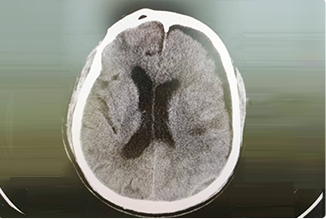

精通颅内动脉瘤介入栓塞和手术夹闭双技术,系统掌握脑动静脉畸形、颈内动脉海绵窦漏、硬脑膜动静脉漏等颅内血管疾病的诊疗和手术,精通颈动脉、椎动脉狭窄的血管内重建技术,以及颈动脉狭窄的内膜剥脱手术技术。在颅内肿瘤、椎管内肿瘤、颅脑损伤、高血压脑出血等疾病的诊治和手术,脑功能性疾病立体定向手术治疗等方面也积累了丰富的经验。

擅长脑血管病(出血与缺血)的神经介入与微创手术,能熟练开展脑外伤、重度颅脑损伤的救治工作。